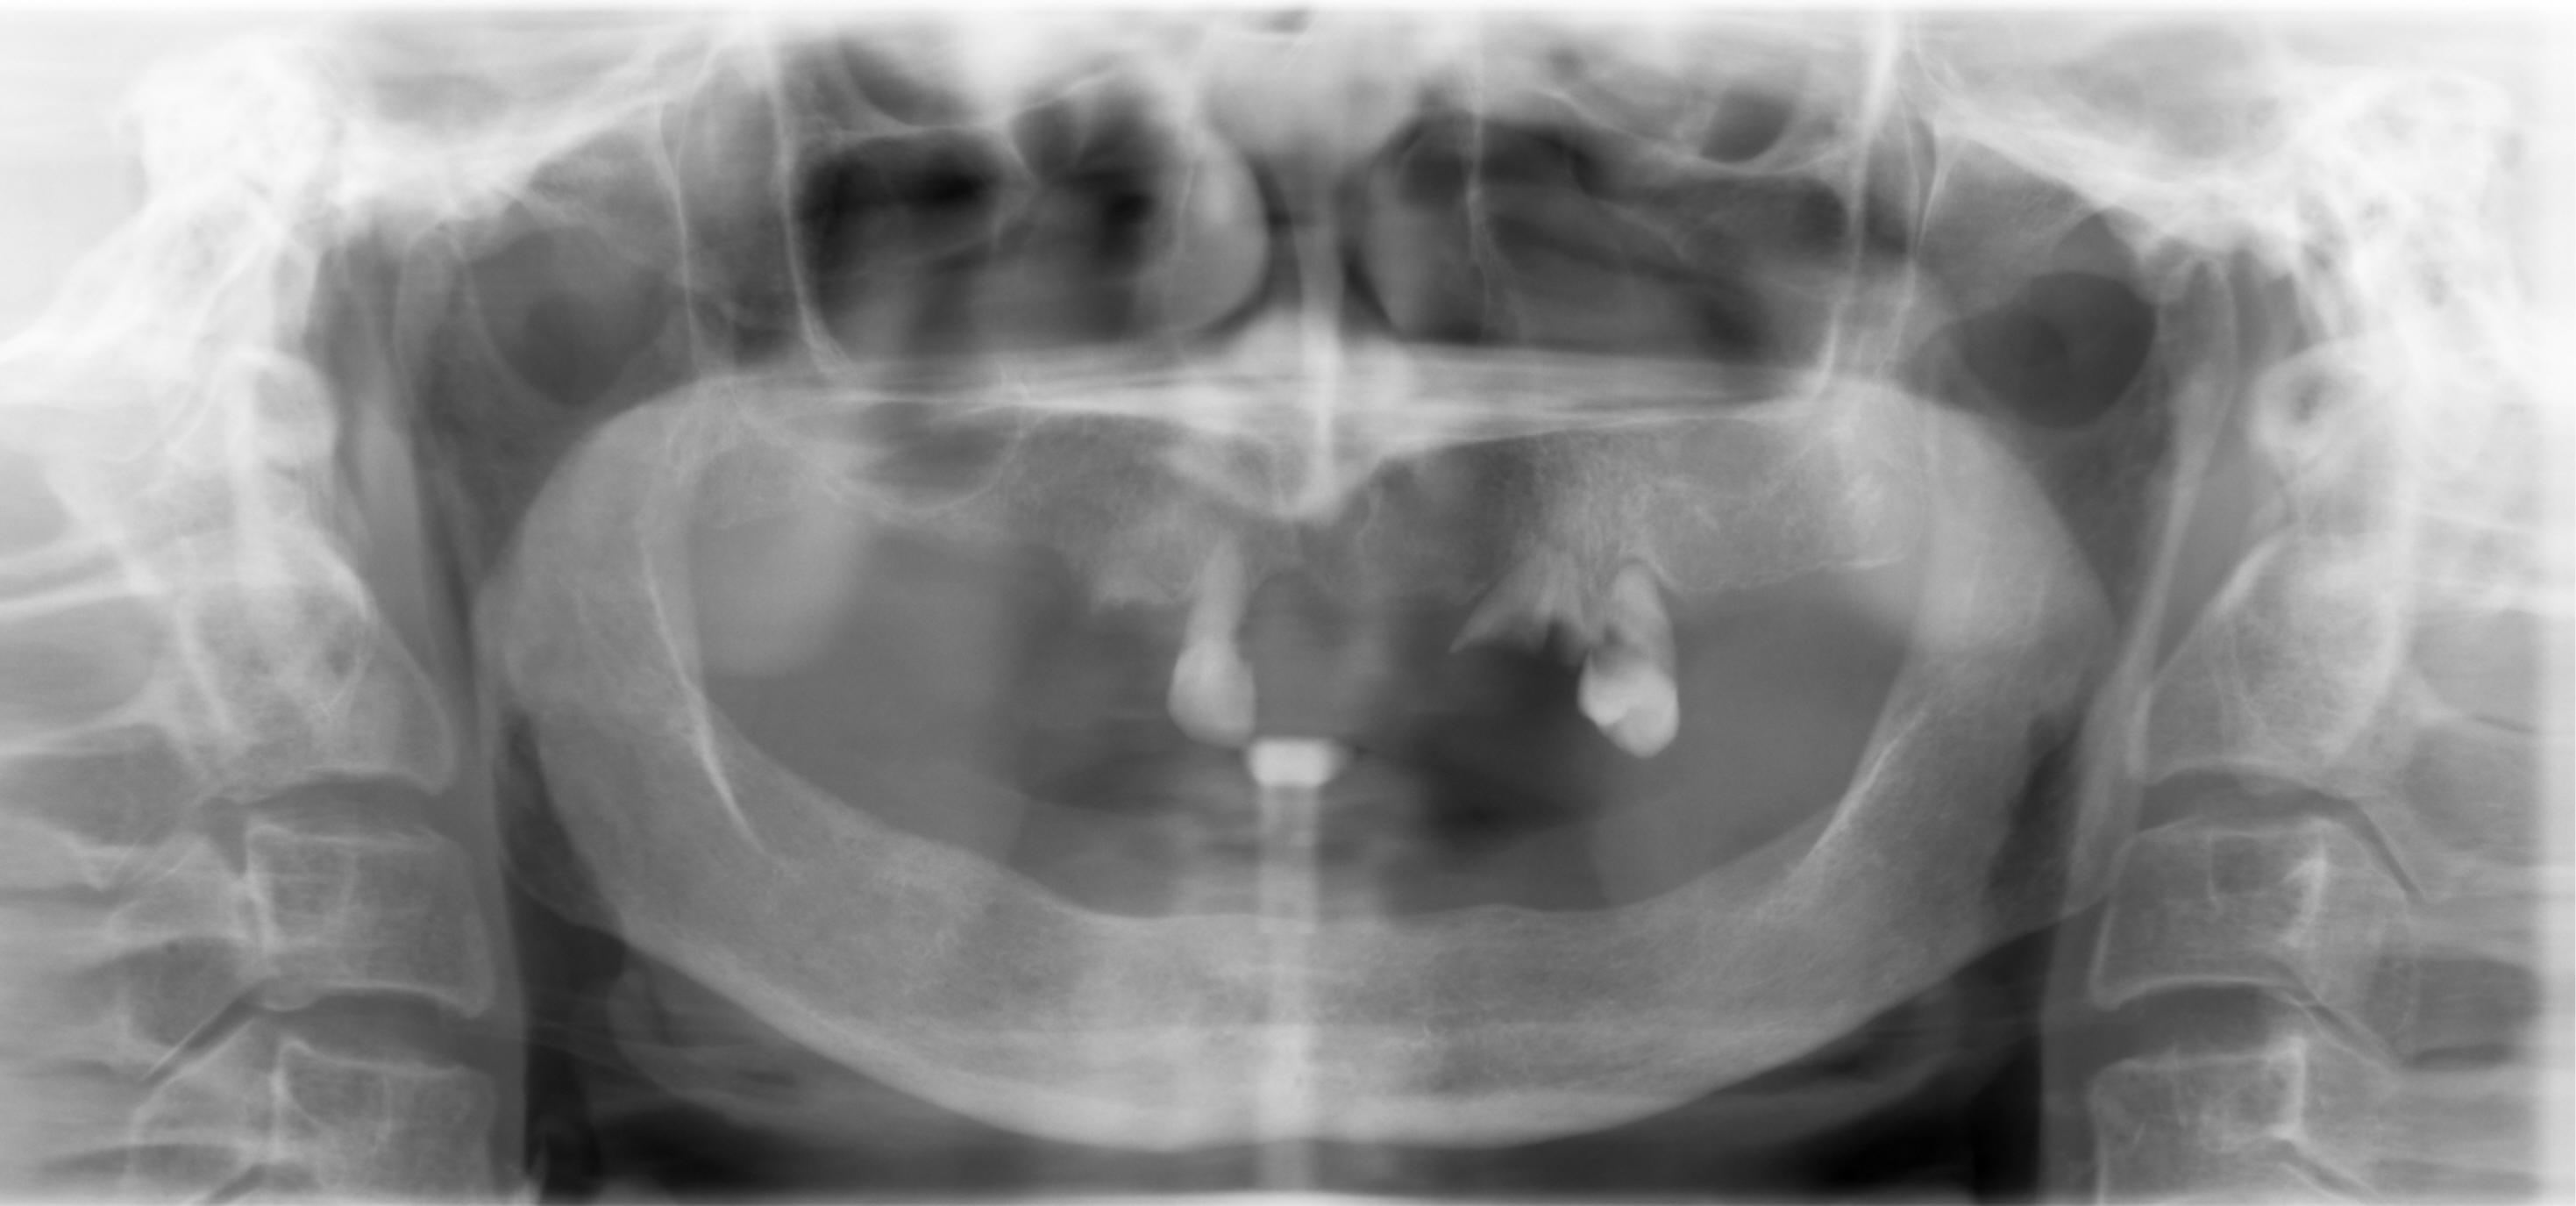

全口拔牙前

74岁太太患有高血压(药物控制)肾衰(透析),上口局部托牙,下口全口义齿,要求拔除其余牙齿,回国做假牙。尽管她和女儿已经下定决心,我们还是提出植牙治疗方案。最后拔牙,牙槽嵴修正术,褥式缝合。如果今后牙槽嵴萎缩严重,再提出植牙,接受就容易些。